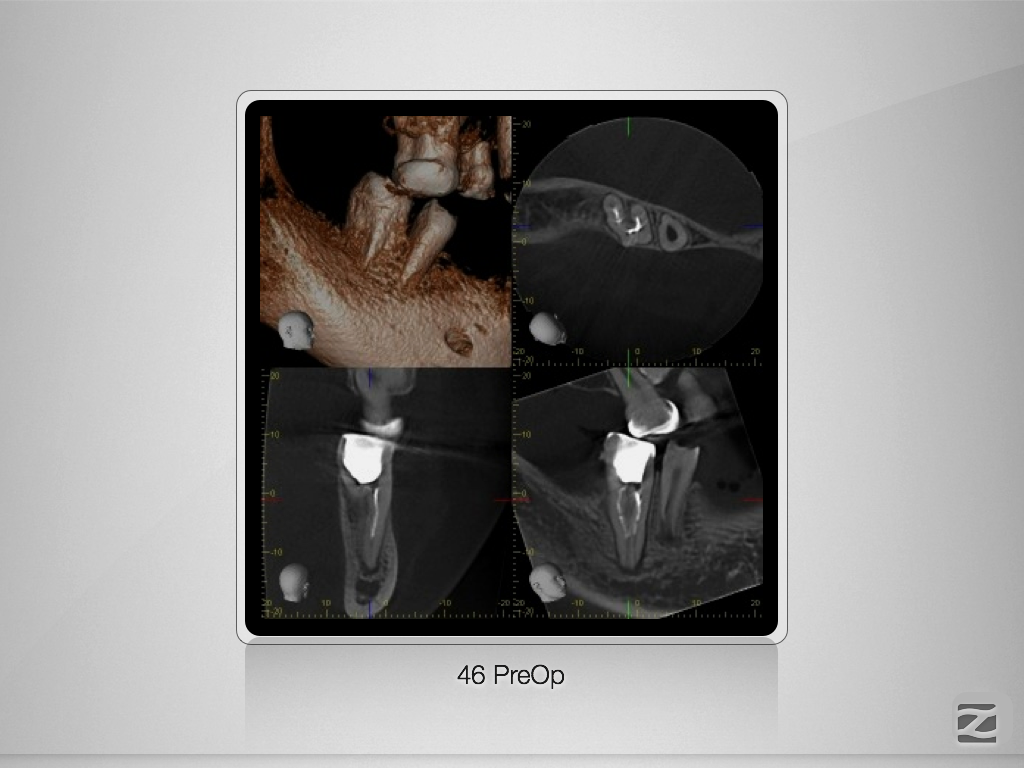

46D.003

Doppeltes C